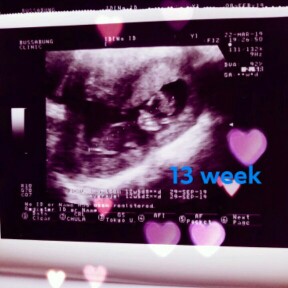

ในรูป 13 w ตอนนี้ 27 แล้วค่ะ